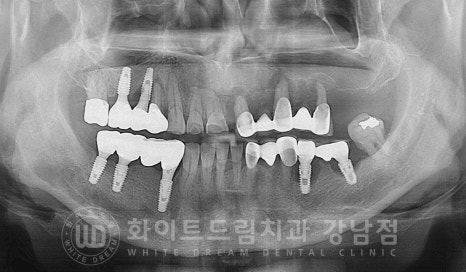

환자분의 초진 구내 사진입니다.

현재 임플란트가 식립되어 있는 10번대 어금니, 30번대 어금니 부위에

심한 염증과 골소실이 일어나 있는 상태입니다.

이 외에도 치주염으로 20번대 브릿지 부위의 상태도 굉장히 좋지 못한 상태인데

임플란트의 상태부터 자세히 보겠습니다.

임플란트 재수술의 주원인 / 찢어짐 & 주위염

10번대 어금니 부위는 임플란트가 찢어지면서 주위 염증이 생겨있고

40번대 어금니는 임플란트 주위염으로

증상은 모두 '임플란트 흔들림'이 발생하고 있는데요.